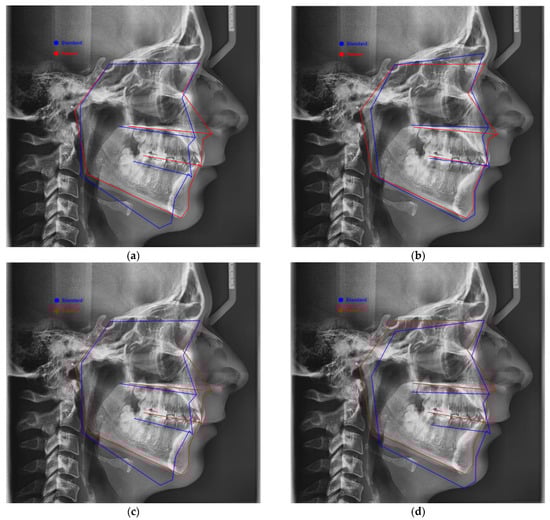

2.1.1. Digital Lateral Cephalometric Measurements and Protocol